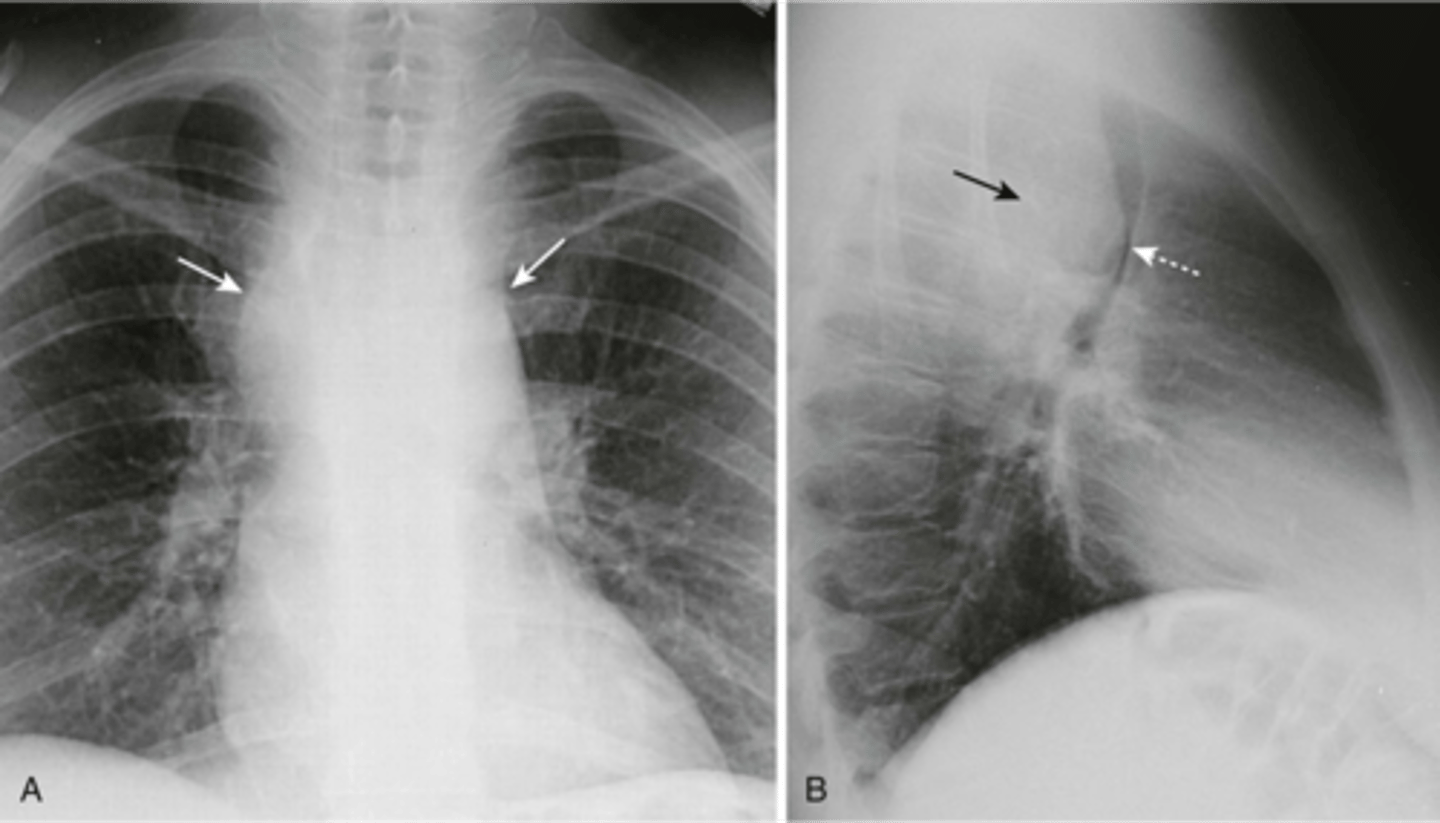

-embolus fills both pulmonary arteries (left side)

-right picture is a small embolus

How does a saddle embolus appear